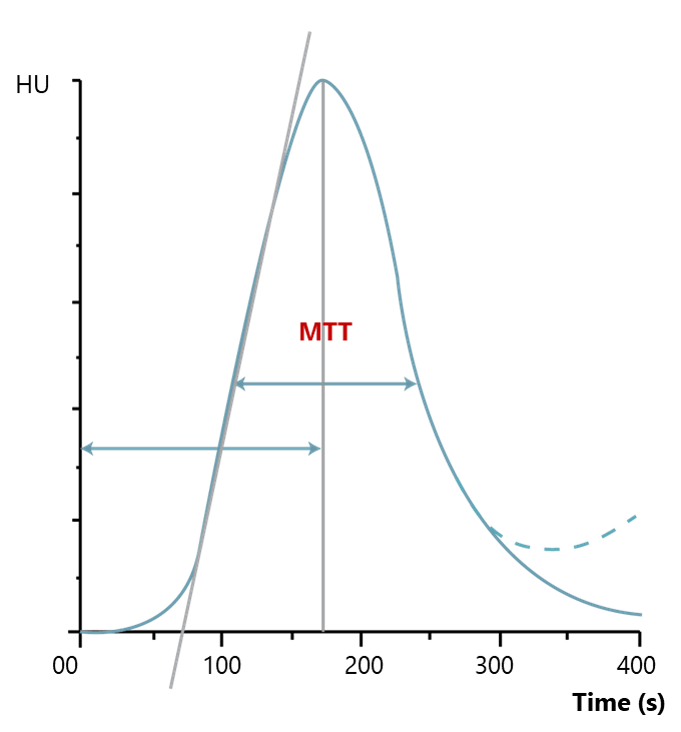

Mean Transit Time (MTT)

The third main parameter to take into consideration is the Mean Transit Time. MTT is measured in seconds and defined as the average amount of time it takes blood to transit within the blood vessels in a particular region of the brain. In brain imaging, maps of MTT are the most commonly used in clinical situations.

Prolonged MTT value in the context of normal CBF means that the affected tissue could remain in this intermediate state indefinitely without a threat to viability and the appearance of clinical symptoms. Alternatively, if the CBF is low, the integrity of the tissue and the clinical response may be compromised, depending on the severity of the reduction in CBF.

A better approach is to combine perfusion CT with CT angiography to monitor hemodynamics in patients with SAH. On perfusion CT, any arterial territory with prolonged MTT is known to be a potential site for vasospasm.

In cases where arterial regions produce MTT and CTA maps suggestive of vasospasm, cortical CBF levels can be checked via perfusion CT. Patients who are positive can be followed with an angiogram for possible endovascular therapy. This approach is more sensitive and specific than Doppler alone, and presents the advantage of eliminating the need for invasive angiograms.